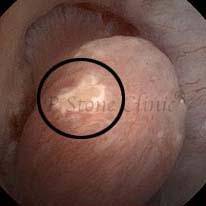

Kidney stone is a solid mass of CRYSTALS. It is the process of crystallization which initiates the formation of kidney stones. This happens in nephrons or units of kidney. Once a small crystal is formed, it can both grow & unite with other crystals leading to the formation of small concretion which eventually forms a stone. Once these large crystals detach from the collecting ducts, the process of stone formation starts in the renal collecting system. A recurrent kidney stone former is advised to know a little bit about something known as Randall’s plaque. Alexander Randall discovered plaques on the renal papillae eight decades back based on examination of 1154 pairs of autopsied Kidneys. He described these renal papillary lesions as cream colored or milk patch areas composed of calcium phosphate & calcium carbonate. These plaques could act as NIDUS for formation of KIDNEY STONE. Calcium Oxalate stone can form on this nidus & then detaches from this plaque to become a free floating stone in the collecting system of kidney

These images are taken as snap shots from the video recording of RIRS Surgery done at our hospital. These are Randall’s Plaques seen with Digital FLEX XC & Digital FLEX XC S. The cream or whitish patches are seen on the tips of RENAL PAPILLAE as seen in images below.

Randall’s Plaques may lead to the formation of Stones.

Those kidney stone patients who have Randall’s Plaques in their kidneys are more likely to form stones again (Recurrent Stones).

Stone Patients in whom Randall’s Plaques are detected at the time of RIRS Surgery should undergo regular ultrasound examination for early detection of stones.

Patients of Stones with Randall’s Plaques in their Kidneys should drink plenty of fluids in addition to Orange Juice & Lemonade.